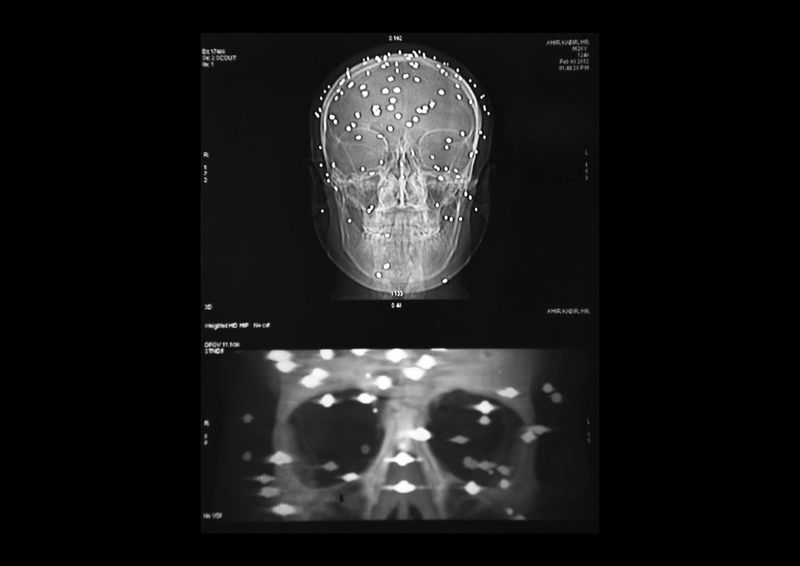

Danish Rajab Jhat, 24 years old, Srinagar. “It was evening time and the police was chasing the stone thrower in my neighborhood. I was just sitting on the side of the road and they shot me. I don't remember anything about that moment, i woke up in the hospital. The left eye was entirely damaged so the doctors replace it with an arti cial eyeball”. A shell entered through the left eye and the pellets dispersed all over the the head damaging also the righ eye. Danish has still 90 pellets inside hi body and from the right eye he can barely see shadows.

i